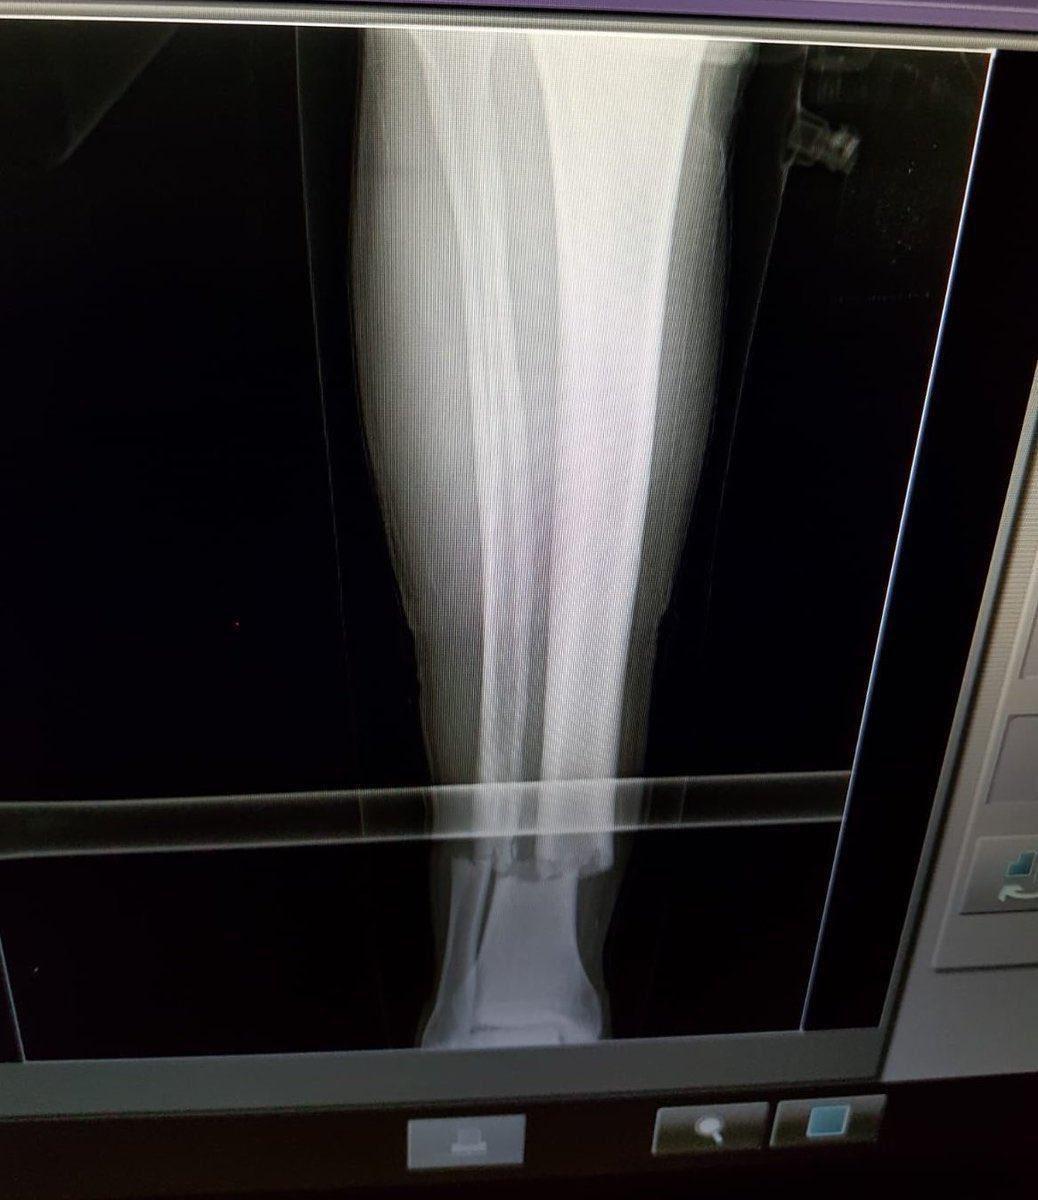

Galatasaray Kulübü, Çaykur Rizespor mücadelesinde sakatlık geçiren Emre Akbaba ile ilgili bir açıklama yayımladı. Açıklamada Emre Akbaba'nın kaval ve baldır kemiklerinde kırık tespit edildiği kaydedildi.